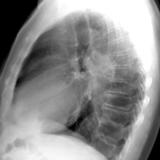

RLL collapse 4 Lat

Date: 03/02/2006

Views: 3166